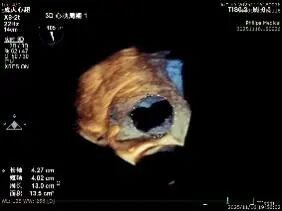

Echocardiographic Assessment: Echocardiography revealed left atrial enlargement. The left atrial appendage (LAA) orifice was 32mm with no thrombus inside. Tricuspid regurgitation was extreme (average vena contracta 18mm). Regurgitant jets were located at the anterior-septal, central, and posterior-septal commissures, with a central gap measuring approximately 13x5.9mm. The annulus was mildly dilated (average diameter 43mm). The tricuspid leaflets showed thickening and degenerative changes.

Systolic Tricuspid Annulus: Circumference 138mm, Area 1468mm².

Diastolic Tricuspid Annulus: Circumference 145mm, Area 1646mm².

Annular area reduction: 50%

preoperative

postoperative

- Annulus Area Reduction: Decreased by 50%.